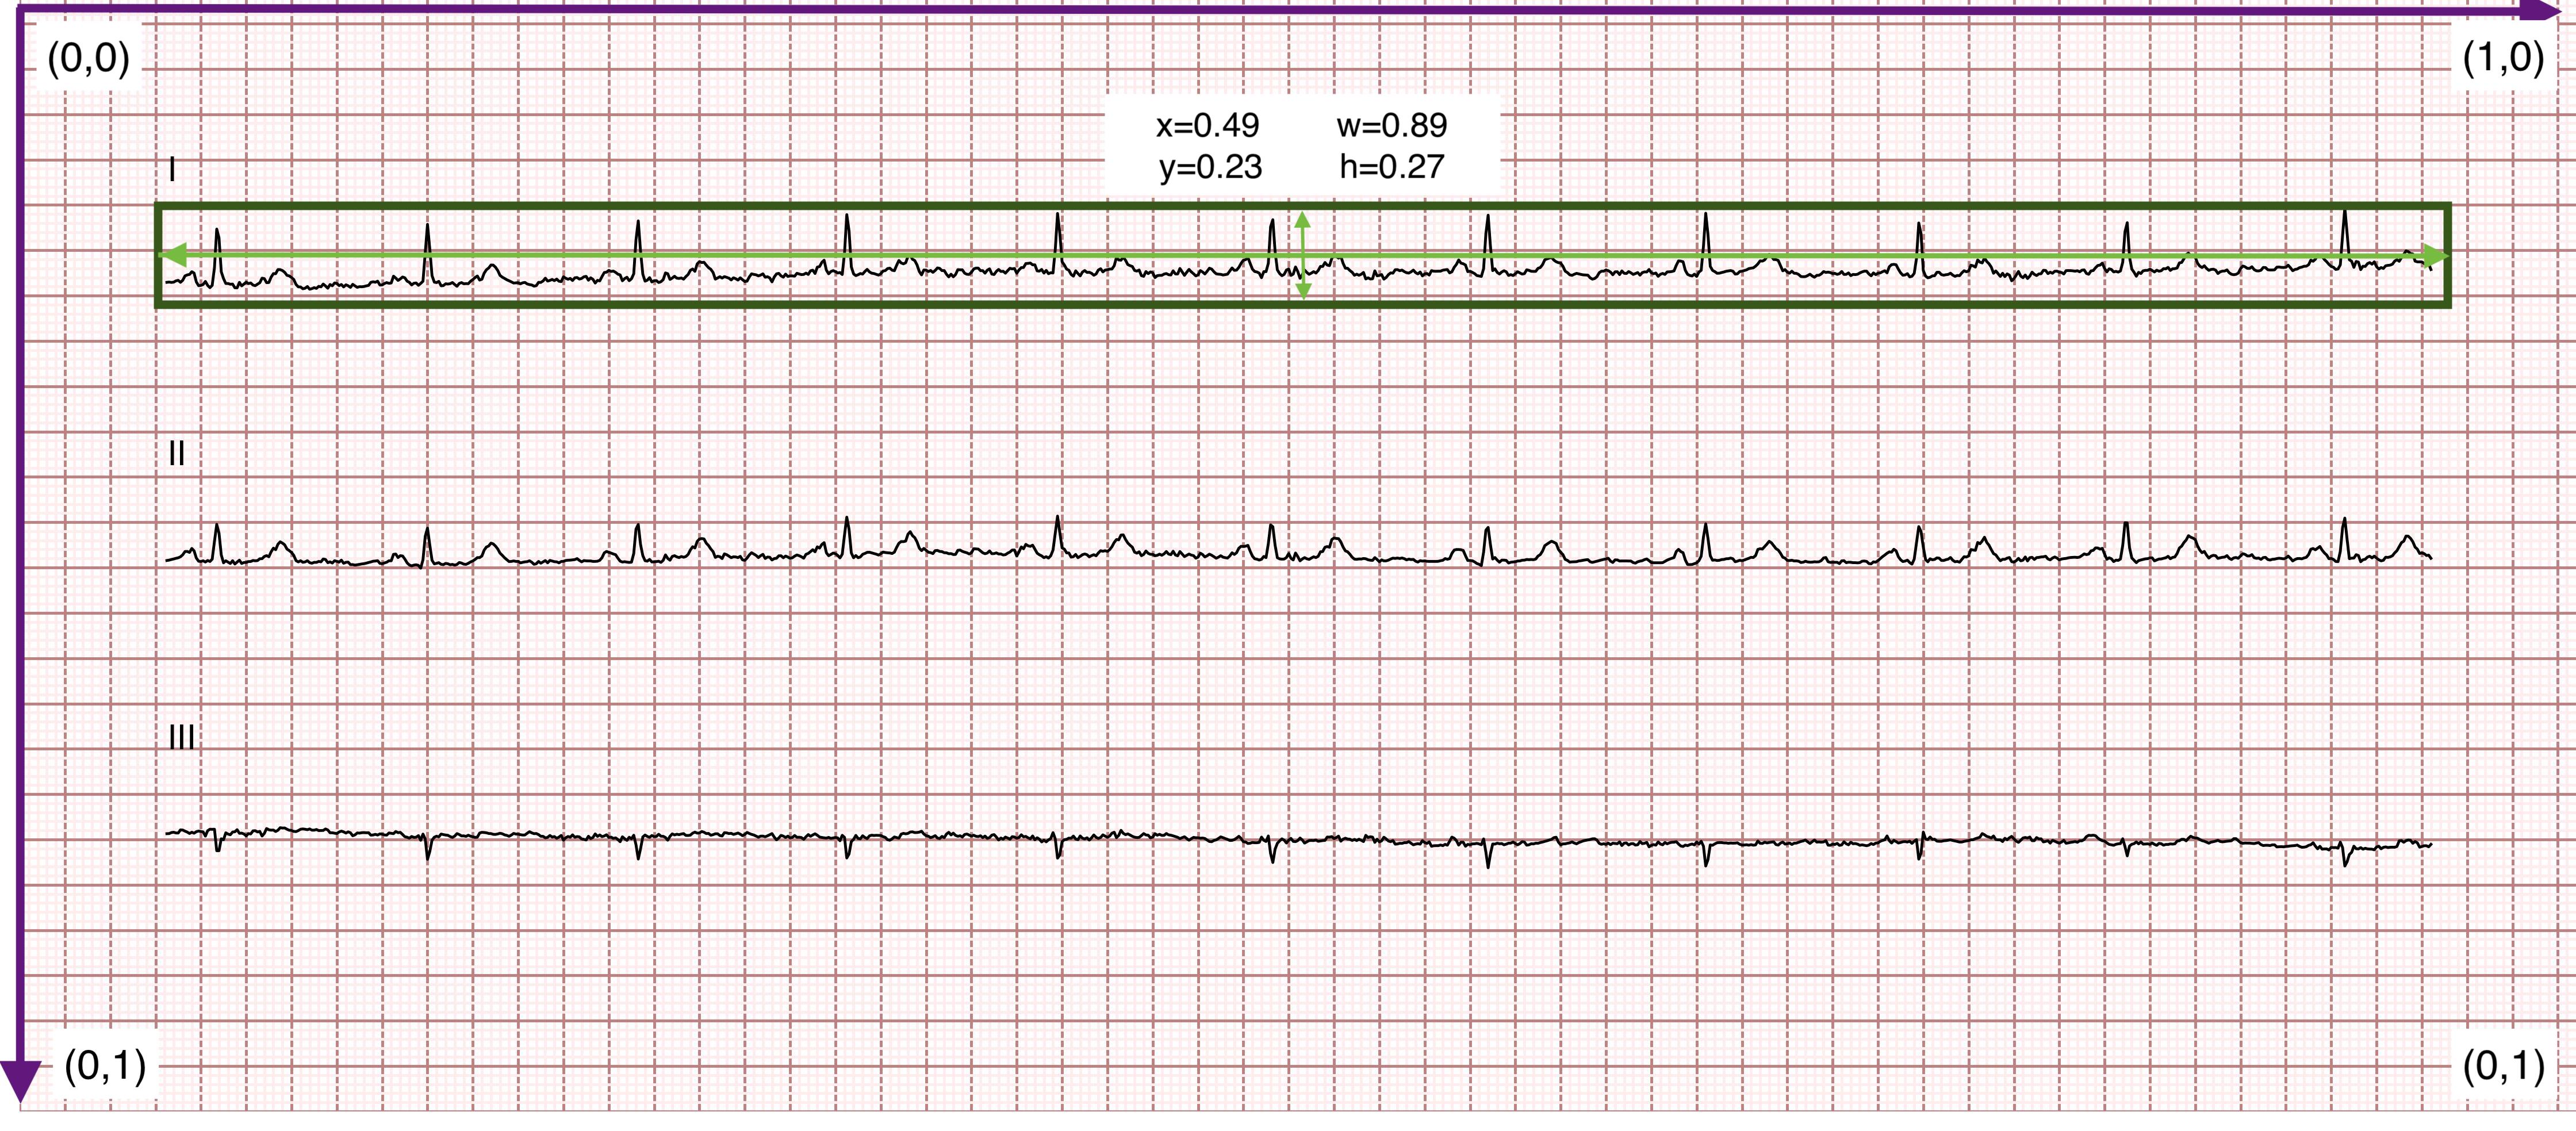

The detection dataset includes 2,000 samples annotated in YOLO format for lead region and lead name detection in ECG images. Figure 3 demonstrates ECG images with different lead layouts and bounding boxes for the lead region and lead name. Each annotation is stored in a .txt file, with one line per object in the image. Each line contains five values: the class index as an integer (c𝑐citalic_c), the normalized coordinates of the bounding box center (x,y)𝑥𝑦(x,y)( italic_x , italic_y ), and the normalized width and height (w,h)𝑤(w,h)( italic_w , italic_h ), all expressed as ratios relative to the image dimensions. The top-left corner of the image is treated as the origin, with the positive x𝑥xitalic_x-axis extending to the right and the positive y𝑦yitalic_y-axis extending downward (see Figure 4). The class index (c𝑐citalic_c) indicates the type of annotated object: c=0𝑐0c=0italic_c = 0 denotes lead waveform regions, while c=1𝑐1c=1italic_c = 1 to c=12𝑐12c=12italic_c = 12 correspond to the 12 lead names (I, II, III, aVR, aVL, aVF, V1–V6). For example, a bounding box with c=1𝑐1c=1italic_c = 1 identifies the ”Lead I,” and c=9𝑐9c=9italic_c = 9 corresponds to ”V3.”

Figure 4: Illustration of the YOLO bounding box format, which includes the class ID, normalized center coordinates (x,y)𝑥𝑦(x,y)( italic_x , italic_y ) and the bounding box width and height (w,h)𝑤(w,h)( italic_w , italic_h ), all expressed relative to the image dimensions